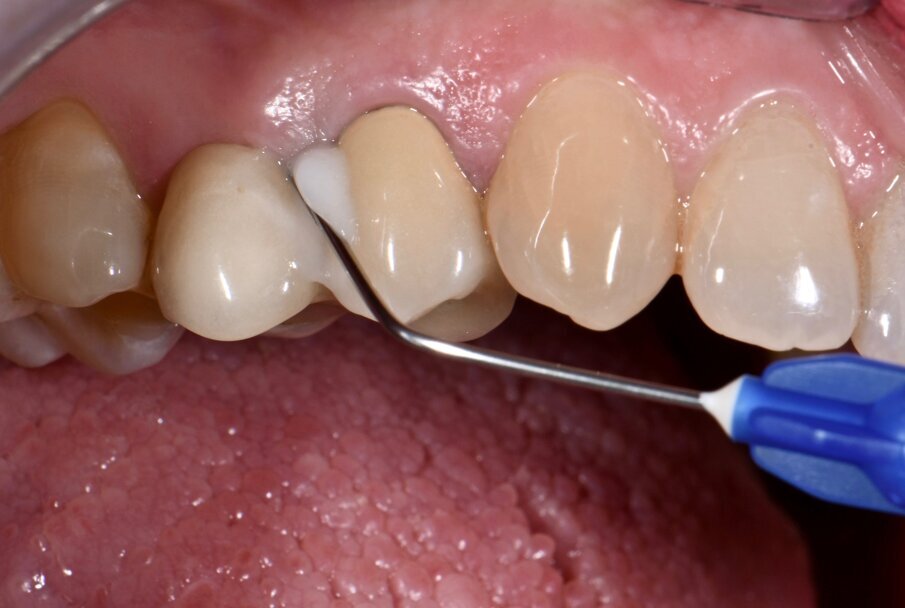

Non si evidenziava trauma occlusale o abitudini parafunzionali. La valutazione radiografica (Fig. 3) aveva rilevato una lieve perdita di osso marginale (MBL) distale dell’impianto 15. L’impianto 25 non era affetto da riassorbimento osseo. In accordo con il World Workshop of Peri-Implant Case Definitions12 del 2017, al paziente era stata fatta una diagnosi di mucosite peri-implantare per l’impianto 25 e di peri-implantite in fase precoce sull’impianto 15. Il difetto osseo a carico dell’impianto 15 può essere classificato come Classe Ia (difetto infraosseo - deiscenza buccale) Grado S (<25% della lunghezza dell’impianto)13. La paziente è stata trattata con una terapia parodontale e peri-implantare non chirurgica con applicazione topica di antimicrobici. Il full mouth debridement comprendeva ablazione del tartaro tramite strumenti a ultrasuoni e strumenti manuali. In particolare, sugli impianti, sono stati utilizzati delle curettes in titanio e un dispositivo air-polishing con polvere di eritritolo (Air-Flow Plus, EMS). Successivamente, è stata eseguita un’applicazione topica di XAN-CHX gel (Chlosite, Ghimas) all’interno dei solchi gengivali di entrambi gli impianti con un ago non traumatico dalla punta smussa (Fig. 4).

Fig. 4 - Applicazione di gel a base di Xantano e Clorexidina (Chlosite) su impianto #15.

Dopo aver inserito l’ago nella tasca peri-implantare, il prodotto è stato applicato con una leggera pressione, riempiendo la tasca. Infine, è stato consigliato alla paziente di non bere e non sciacquare per un’ora dopo l’applicazione. I parametri peri-implantari sono stati registrati a 30-60-90 giorni. Durante le stesse sedute, dopo la lucidatura delle superfici tramite dispositivo air-polishing, sono state eseguite le applicazione di XAN-CHX gel. I parametri clinici parodontali e peri-implantari sono stati rilevati a 6 mesi e a un anno prima di aver effettuato un debridement sopragengivale.